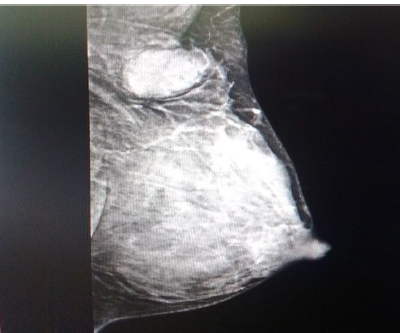

Case report primary neuroendocrine carcinoma of breast

Osaid Shoail, Alhareth Azaizeh, Mothana Alnawaflh, Duha Al-khamaiseh, Tariq Alomari, Oadi Al-wraikat

International Journal of Scientific Research and Management (IJSRM)  |  Published: 2 November 2025